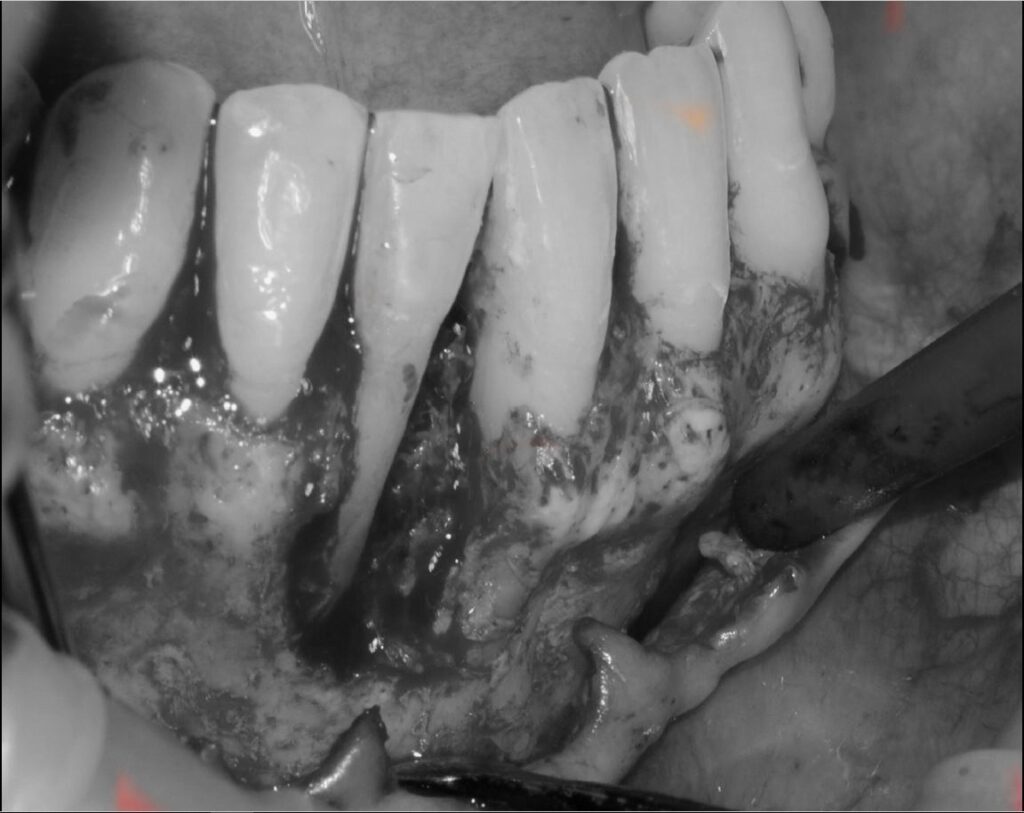

R.A.R. Profundo suave intraquirúrgico

Aplicación protocolo emdogain

Regeneración ósea guiada con membrana de colageno creos de Nobel Biocare y relleno óseo mediante BIOSS Collagene de INIBSA, con elementos de fijación a la membrana para R.O.G.

Fotografías del proceso: